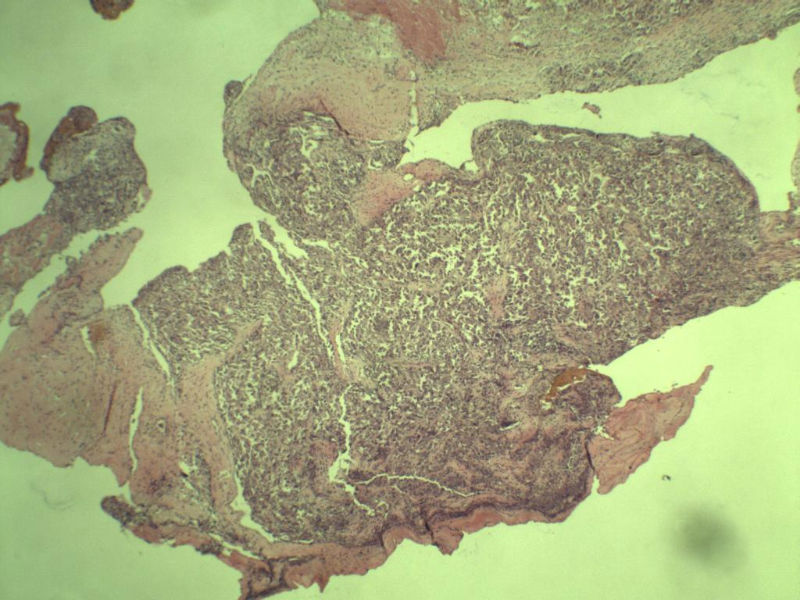

女 70岁 右颈部 头皮 多发皮下结节      取颈部部分结节送检 灰白小组织 1 块,直径 0.4 cm。 请问这个是什么?

肿瘤细胞大,上皮样,核空泡状,核仁明显,胞质嗜酸性或透明。

考虑:恶性黑色素瘤?

近心型上皮样肉瘤?

软组织透明细胞肉瘤?

上皮样多形性脂肪肉瘤?

等免疫组化标记!

此片染色欠佳,取材或切面也有问题,加大了诊断的难度,恶黑确实需要考虑,但其他一些转移癌也需要排除,比如肺癌之类的,还是期待免疫组化!